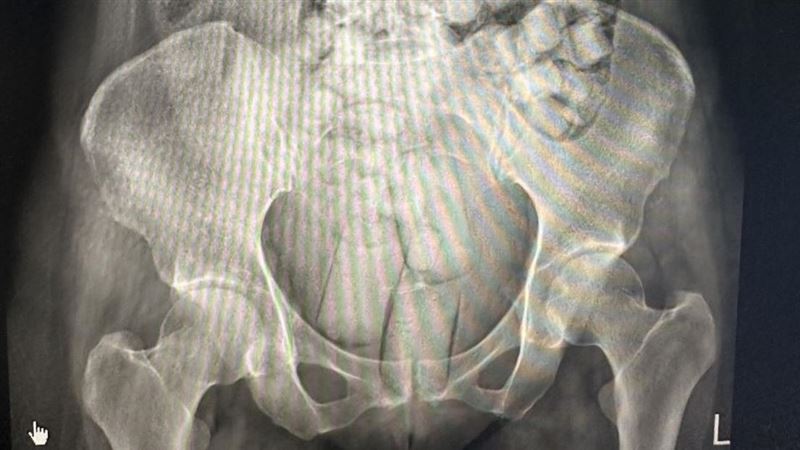

販毒集團先將海洛因毒品分裝在可吞食的橢圓形顆粒,或方便塞入私密處之長條狀,再以保險套或乳膠膜等耐腐蝕性及防水之外袋包裹後,讓2名泰國女子自行加橄欖油吞食及塞入肛門,將毒品夾藏體內規避安檢,鋌而走險從泰國搭機運毒走私來台。

2名泰國女子聲稱,在泰國曼谷透過不知名的泰國人士介紹到台灣旅遊,出發前對方先給了1000元美金,等到順利入境後,會有人打電話聯絡,到時候再約見面交付毒品,給予12萬及8萬酬勞。不料兩人於9月7日一入境台灣小港機場,當場被查出體內夾藏毒品,被帶往醫院排出海洛因毒品,共115顆、重量達664公克。